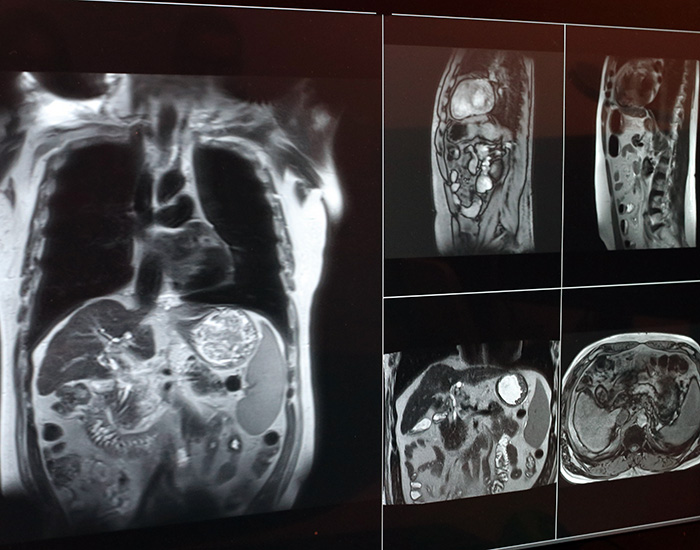

radiation image 700

Image taken on

Apr 7, 2026, 13:17 by Tonia Twichell